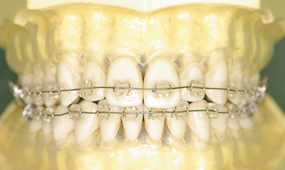

- メタルブラケット装置

メリット

- ・装置自体が金属性で強度が高いので小さく出来ている為、違和感が少なく口内炎もできにくい。

- ・強度が高いので壊れたり、外れたりし難いので治療期間が長引く可能性が少ない。

- ・装置とワイヤーが金属同士なので滑りが良く歯が動きやすいので治療期間が短く出来る。

- ・強度が高いので強い力をかけても壊れにくい為強い力で正確に歯をコントロールでき、より良い治療結果を得る事ができる。

デメリット

- ・装置が目立つ